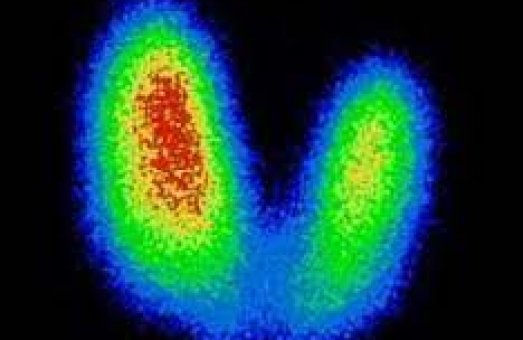

Пацієнтові вводять спеціальну речовину, в складі якої є радіонуклід, що підбирається індивідуально для певного органу чи тканини. Цей радіонуклід випромінює гамма-кванти, які фіксуються сучасною апаратурою. Важливо підкреслити: променеве навантаження при цьому у 100 разів менше, ніж при звичайному рентгені. Це робить метод безпечним навіть для ослаблених пацієнтів. У результаті лікар отримує зображення, які відображають не лише структуру органу (як при УЗД або МРТ),а й його функціонування на молекулярному рівні. Завдяки цьому патологічні процеси можна виявити на 6–9 місяців раніше, ніж іншими методами. Чим раніше встановлений діагноз — тим більше шансів на успішне лікування.

На відміну від більшості методів, які показують лише будову органу, радіонуклідна діагностика дозволяє оцінити, як він працює.